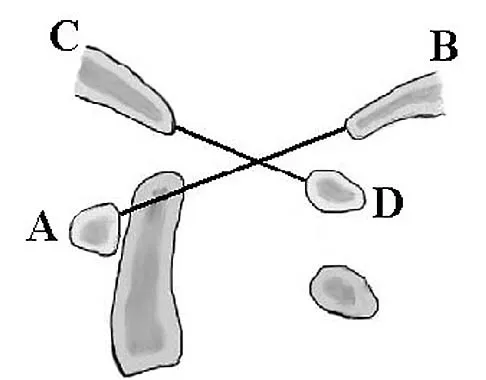

In Figure 49, line AB connects the anterior arch of C1 to the posterior margin of the foramen magnum. Line CD connects the anterior margin of the foramen magnum to the posterior arch of C1. What is the normal ratio of displacement from CD to AB (Power's ratio)?